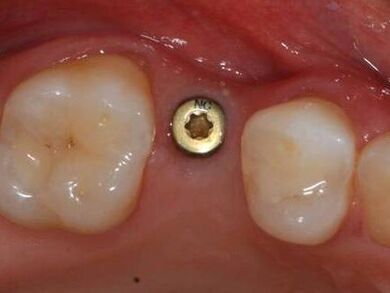

Patientenfall: Versorgung einer Einzelzahnlücke mit einem Implantat